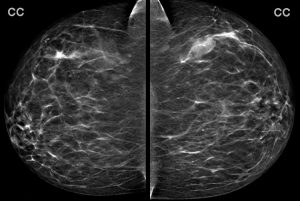

A 40-year-old woman presents for a baseline screening mammogram:

You note a large mass in the left breast. What is the best description for the location of this mass?

Explanation: To interpret a mammogram, one must become familiar with the proper way to describe the location of a finding such as a mass or calcifications. Standard reporting should include the following:

O’clock face is determined by visualizing that you are standing in front of the patient, looking at the breast with a clock superimposed upon it. Note that any o’clock position will not be in the same quadrant of each breast (i.e. a 2:00 mass in the right breast is upper inner quadrant, but a 2:00 mass in the left breast is upper outer quadrant).

Determining the quadrant and o’clock face of a finding requires being familiar with the standard display of a mammogram. If you are not yet familiar with the orientation of a mammogram, see the below annotations: